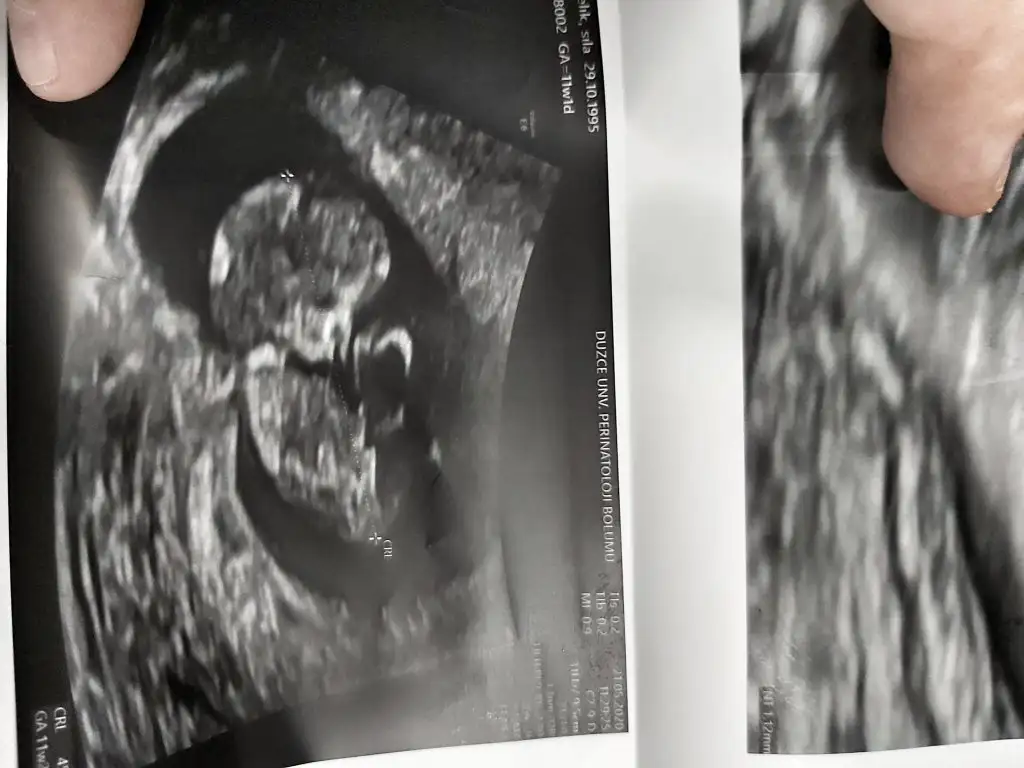

Kızına kız arkadaş geliyor gibi dedi ama haftayi bekleyelim dedi bende dedim ama ilk görüntüsünde sağa yerlesmis dediniz dedim haftaya daha sağlıklı olur bakalım dedi ikrameyra

Hayırlısı olsun cnm bakalım değişicekmi

IMG_20200323_220215.webp